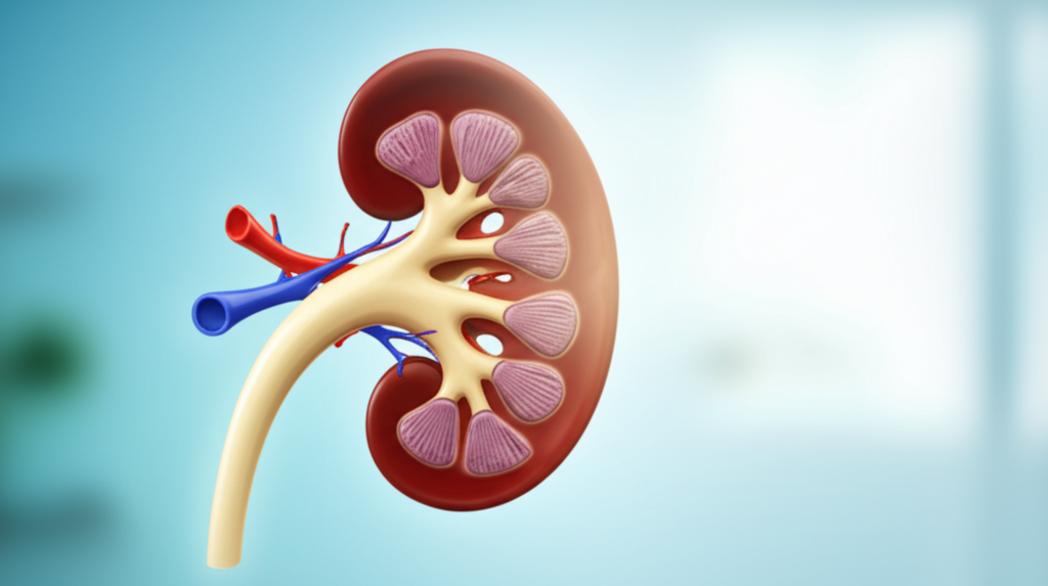

ไตเป็นอวัยวะสำคัญที่ทำหน้าที่กรองของเสียออกจากเลือด รักษาสมดุลของน้ำและเกลือแร่ในร่างกาย และสร้างฮอร์โมนที่จำเป็นต่างๆ เมื่อไตเริ่มทำงานผิดปกติ เราเรียกว่าภาวะไตเสื่อม ซึ่งแบ่งออกเป็นหลายระยะ ตั้งแต่ระยะเริ่มต้นที่อาการไม่รุนแรง ไปจนถึงระยะสุดท้ายที่ไตไม่สามารถทำงานได้เลย การตรวจพบภาวะไตเสื่อมตั้งแต่เนิ่นๆ เป็นกุญแจสำคัญในการรักษาและชะลอความเสียหาย โดยเฉพาะในระยะที่ 1-3 ซึ่งเป็นระยะที่ยังมีโอกาส ฟื้นฟูไต และควบคุมไม่ให้โรคดำเนินไปสู่ระยะรุนแรงได้ดีกว่า สัญญาณเตือนของไตเสื่อมมักไม่ชัดเจนในระยะแรกๆ แต่สามารถสังเกตได้จากอาการต่างๆ เช่น ปัสสาวะบ่อยผิดปกติ โดยเฉพาะเวลากลางคืน, ปัสสาวะมีฟองหรือมีเลือดปน, อาการบวมตามร่างกาย โดยเฉพาะที่เท้า ข้อเท้า และหนังตา, อ่อนเพลีย เหนื่อยง่าย, คันตามผิวหนัง, เบื่ออาหาร, คลื่นไส้ หรือมีกลิ่นปากผิดปกติ หากพบอาการเหล่านี้ควรรีบพบแพทย์เพื่อตรวจวินิจฉัยอย่างละเอียด